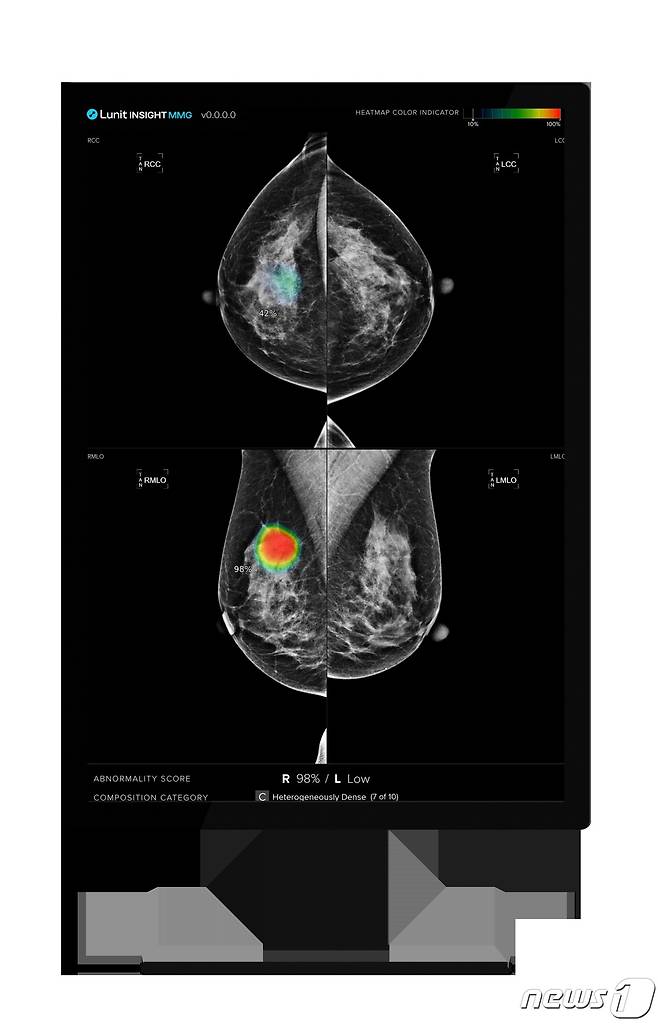

의료 인공지능(AI) 기업 루닛(328130)은 유방촬영술 AI 영상분석 솔루션 '루닛 인사이트 MMG' 활용 시 유방암 조기 진단 가능성을 높이고, 의료진의 업무 부담을 현저히 줄일 수 있다는 연구결과를 유럽 영상의학 학술지 '유럽 방사선학'(European Radiology)에 게재했다고 8일 밝혔다.

(서울=뉴스1) 황진중 기자 = 의료 인공지능(AI) 기업 루닛(328130)은 유방촬영술 AI 영상분석 솔루션 ‘루닛 인사이트 MMG’ 활용 시 유방암 조기 진단 가능성을 높이고, 의료진의 업무 부담을 현저히 줄일 수 있다는 연구결과를 유럽 영상의학 학술지 ‘유럽 방사선학’(European Radiology)에 게재했다고 8일 밝혔다.

이번 연구를 주도한 튀르키예 아치바뎀 메흐메트 알리 아이딘라 대학교(Acibadem Mehmet Ali Aydinlar University) 영상의학과 무스타파 에게 세커 박사(Dr. Mustafa Ege Seker) 연구팀은 지난 2009년부터 2019년까지 튀르키예에서 진행된 2만2621건의 유방촬영술 사례를 분석했다.

연구진은 AI를 활용한 유방암 조기 발견, 간격 암(Interval Cancer) 발견과 함께 AI가 의료진의 업무(Workload) 부담을 얼마나 줄일 수 있는지에 대해 중점적으로 탐구했다.

연구 결과, 의료진의 유방암 검진 워크플로우(Workflow)에서 AI를 유방암 환자 분류(Triage) 도구로 도입했을 때 의료진의 업무량을 약 69.5% 줄여줌과 동시에 분류 정확도는 약 30.5% 향상했다. 루닛 인사이트 MMG 활용 시 전체 간격암의 약 52%, 기존 검진에서 놓쳤던 암의 약 50%를 바로 식별해 냈다.

유방촬영술 검사에서 영상의학과 전문의 두 명이 참여하는 이중 판독(Double Reading) 상황에서 의사 한명 대신 AI를 두 번째 판독자로 활용할 경우 전체 유방암 환자의 약 23%를 평균 약 30개월 더 빠르게 진단했다.

루닛은 이번 연구는 AI 기술이 유방암 검진 과정의 효율성을 크게 개선하고, 조기 진단율을 높임으로써 환자의 생명을 구하는 데 중요한 역할을 할 수 있음을 잘 나타낸 것이라고 설명했다.

서범석 루닛 대표는 “이번 연구는 AI 영상분석 솔루션의 임상적 유용성 뿐만 아니라 의료 시장의 성장 잠재력이 크고, 의료 제품 수입 의존도가 높은 튀르키예에서 성능을 입증했다는 점에서 향후 비즈니스 확장 가능성도 기대하고 있다”면서 “앞으로도 글로벌 의료진과의 다양한 협업을 통해 의료 AI의 적용 범위를 확대해 나갈 것”이라고 말했다.